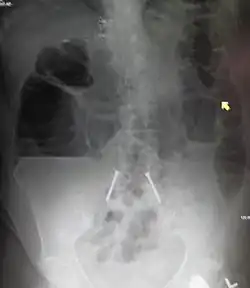

Upright abdominal X-ray demonstrating a small bowel obstruction. Note multiple air fluid levels.